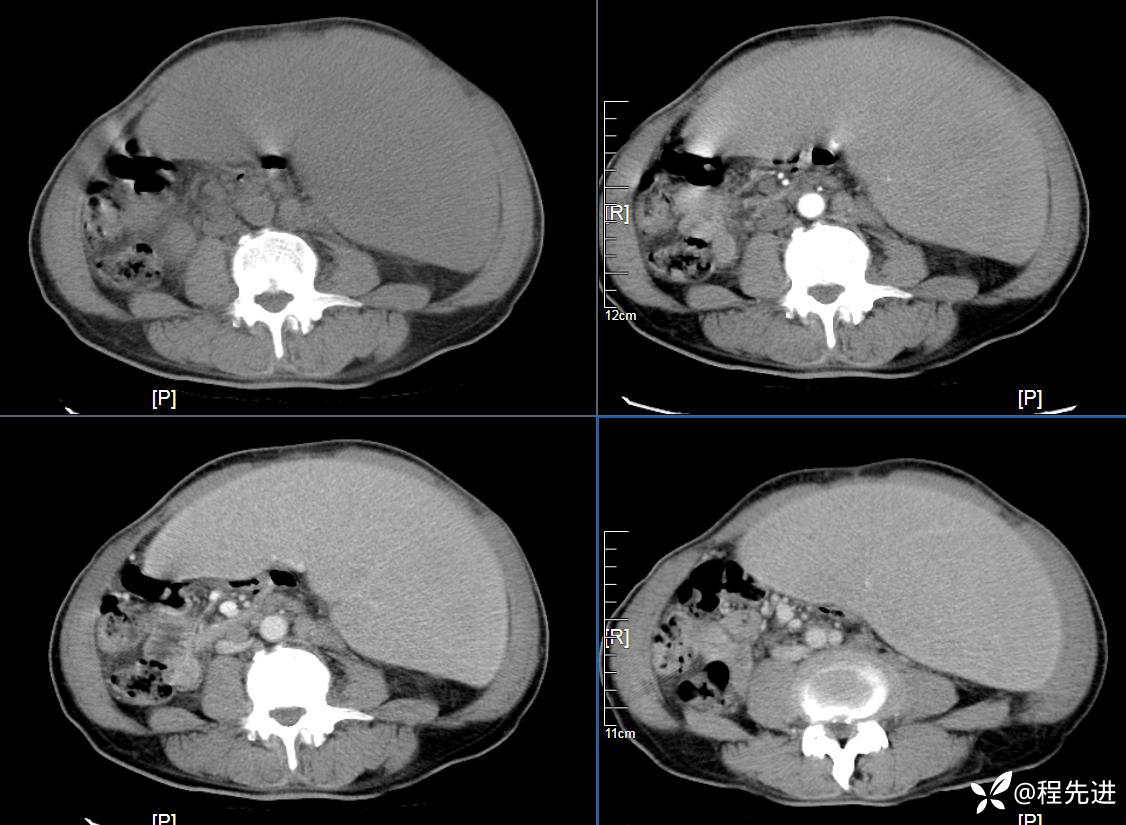

患者性别:男

患者年龄:59岁

简要病史:体检发现脾脏肿大半月

CT平扫及增强3期: